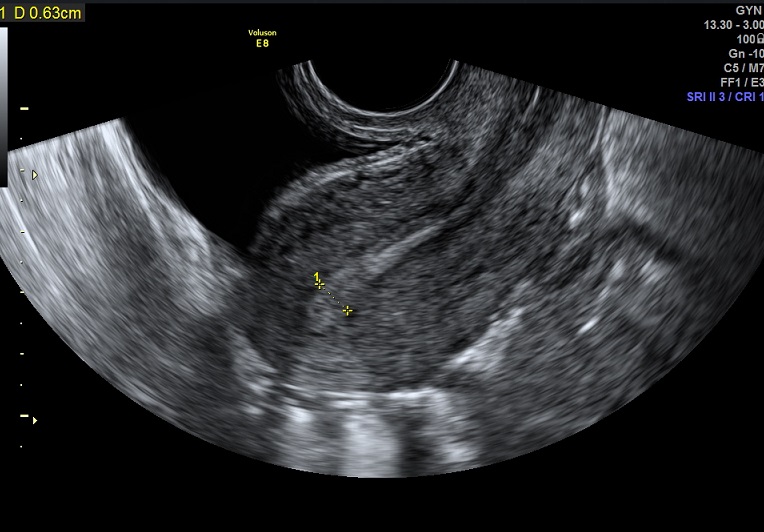

2015-3-19 月经第24天检查 内膜厚0.6cm 内膜血流:1级 内膜波动不明显 左卵巢黄体 子宫动脉: L:PSV:27.3cm/s EDV:4.7cm/s RI:0.83 S/D:5.8 PI:2.5 R: PSV:28.8cm/s EDV:2.0cm/s RI:0.93 S/D:14.4 PI:3.8 舒张早期血流缺失 检验: 2015-3-11 E2: 155.42 LH: 7.00 FSH: 4.43 P: 2.45 |

2015-3-19图示